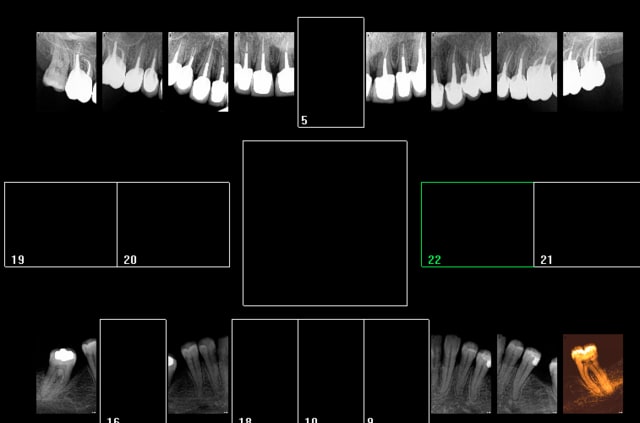

X ray 03 medium zvq18j - Eugenol